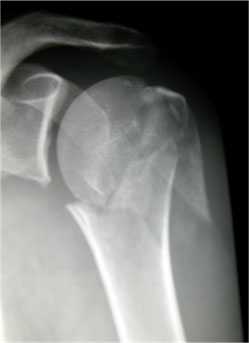

Рис. 1. На рентгенограммах: оскольчатый перелом проксимального отдела плечевой кости со смещением отломков.

Переломы проксимального отдела плечевой кости расположены проксимальнее хирургической шейки кости (см. рисунок Основные анатомические ориентиры в проксимальном отделе плечевой кости Основные анатомические ориентиры в проксимальном отделе плечевой кости ). Большинство из них сопровождаются минимальными смещением и поворотом отломков. Диагноз устанавливают по данным обзорной рентгенографии или, иногда, КТ. Большинство из этих переломов можно лечить наложением повязки, пращевидной повязки, с ранней мобилизацией.

Перелом хирургической шейки плечевой кости.